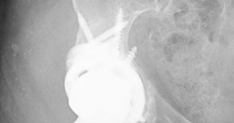

History of presenting complaint : Presents with a draining wound and well-fixed cementless components with a constrained liner due to absent abductor mechanism (Fig. 19.12). Treated with Prostalac and six weeks of IV antibiotics (Fig. 19.13). At the 6-week point, the patient sustained a ground level fall with an acetabular fracture and displacement of the acetabular Prostalac (Fig. 19.14).

Fig. 19.12 AP X-ray right THA with well-fixed components and severe osteoporosis with healed inferior pubic ramus fracture